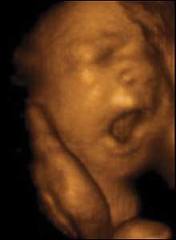

Il pancione è cresciuto ancora e non permette di vedere neanche i piedi. Il bambino pesa circa 2 kg ed è lungo circa 38 cm. Ogni settimana metterà su tra i 200 e i 250 gr e diventerà sempre più cicciottello. Le ossa cominciano a solidificarsi, esclusa la scatola cranica, che deve rimanere malleabile per permettere la nascita.

Il piccolo continua a crescere e dovrebbe pesare circa 2250 grammi, ma le stime del peso fetale sono variabili e oscillano di circa il 10% in più o in meno a quanto segnalato. Infatti, ora ci si basa su dei calcoli di equazioni matematiche partendo dalle misure ecografiche della circonferenza cranica, della circonferenza addominale e della lunghezza del femore che possono orientare sul peso, ma non darne la certezza.

Il peso del piccolo è arrivato intorno ai 2550 gr., è più rotondo, si muove in rapporto al poco spazio che ha a disposizione e il suo sistema neurologico è ben sviluppato.

Il bambino è arrivato a pesare circa 2750 grammi ed è lungo circa 48 centimetri. Il suo corpicino comincia a perdere la peluria e la vernice caseosa che l’ha ricoperto finora per proteggerlo dall’azione irritante del liquido amniotico. Queste e altre sostanze sono ingerite dal piccolo con il liquido e vanno a formare il meconio.